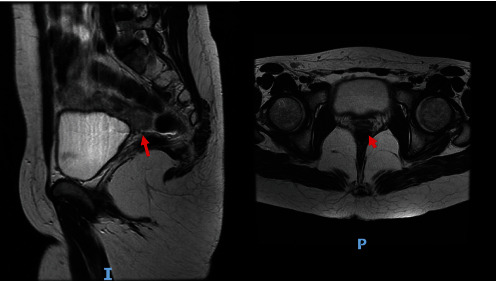

Case: We present the case of a woman who, during the neonatal period, presented salt-losing adrenal insufficiency associated with 46 XY gonadal dysgenesis. The genetic study found a steroidogenic acute regulatory protein (StAR) mutation.

Conclusion: Mutations in StAR result in a nonfunctional protein, which clinically translates into congenital adrenal hyperplasia and, in the case of patients with 46 XY karyotype, is accompanied by gonadal dysgenesis characterized by androgen deficiency, without alterations in anti-Müllerian hormone.